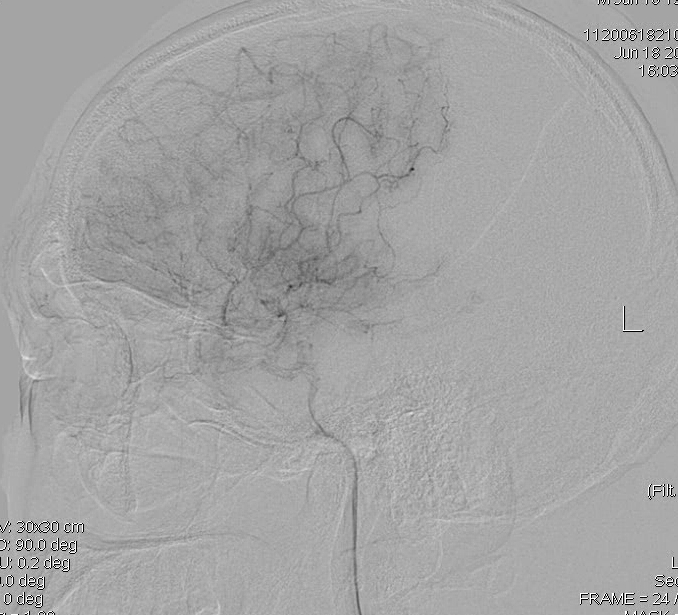

DSA显示右侧颈内动脉末端闭塞:

但是左侧是大脑中动脉闭塞:

所以,第一考虑不是烟雾病。